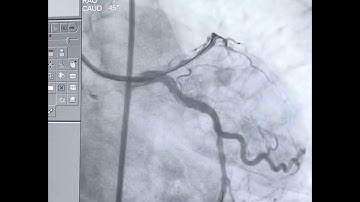

LAD CTO Case 5 , wire de-escalation.